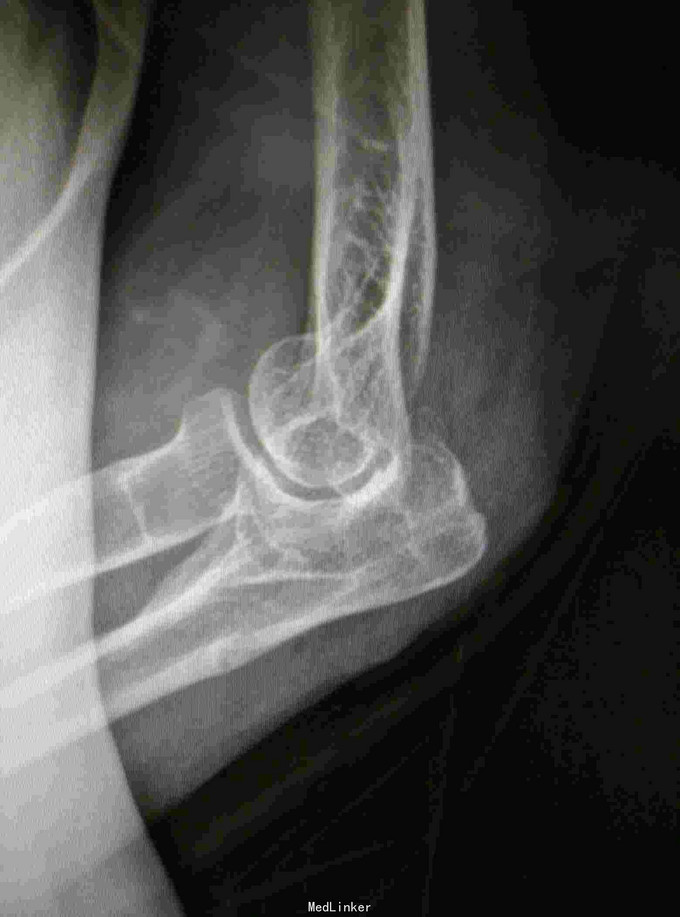

内固定取出术

随访:术后2周手术切口愈合好,肘关节活动度好 讨论: 术后1年骨折愈合后内固定取出较顺利。